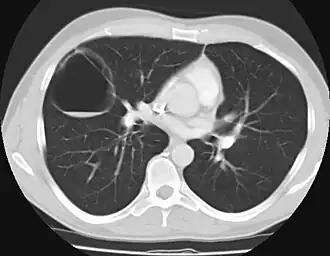

Description de l'image Computerized tomography of the chest of a patient with congenital cystic adenomatoid malformation.jpg.

La maladie adénomatoïde kystique du poumon aussi nommée maladie adénomatoïde du poumon est une pathologie congénitale caractérisée par une prolifération anormale de tissu bronchique avec apparition de kystes pulmonaires. Cette pathologie survient un peu plus fréquemment chez les garçons que chez les filles et atteint n'importe quel lobe pulmonaire. Elle est unilobaire dans plus de 80 % des cas et atteint les deux poumons dans moins de 2 % des cas. Il existe une classification divisant cette pathologie en trois types en fonction de la taille des kystes et de l'aspect de l'épithélium dans ces kystes[1]. Cette classification permet de porter un pronostic.

Le diagnostic post-natal précis repose surtout sur un CT scan ou IRM vers 4-6 semaines, voir plus tôt si le nourrisson ne se porte pas bien. Un Angio-CT est aussi très utile pour évaluer si une séquestration pulmonaire est associée. Si une échographie périnatale est pratiquée, les kystes paraîtront solides jusqu'à résorption du liquide pulmonaire.